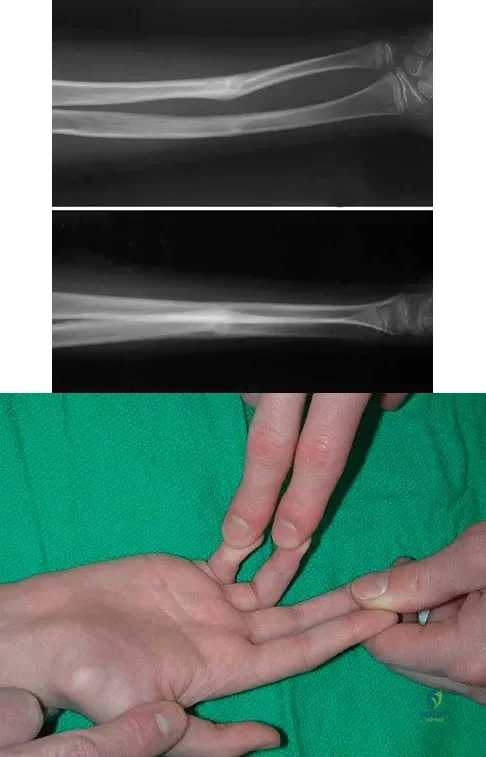

A 12-year-old boy sustained a both bone forearm fracture 10 weeks ago and underwent closed reduction and casting. Examination now reveals that the injury is healed, but he is unable to extend his little and ring fingers of the injured hand with his wrist extended. Full extension is possible with the wrist flexed. A radiograph and clinical photograph are shown in Figures 15a and 15b. The remainder of his hand and wrist examination and neurologic evaluation in the hand are normal. What is the most likely diagnosis?

Explanation:

In this patient, examination reveals an inability to extend the fingers with the wrist extended, but full extension is possible with wrist flexion. These findings demonstrate isolated tenodesis of the flexor digitorum to the ring and little fingers. These findings are not consistent with compartment syndrome or nerve injury. Scarring or entrapment of tendons in forearm fractures can occur. Watson PA, Blair W: Entrapment of the index flexor digitorum profundus tendon after fracture of both forearm bones in a child. Iowa Orthop J 1999;19:127-128. Shaw BA, Murphy KM: Flexor tendon entrapment in ulnar shaft fractures. Clin Orthop 1996;330:181-184. Kolkman KA, van Niekerk JL, Rieu PN, et al: A complicated forearm greenstick fracture: Case report. J Trauma 1992;32:116-117.